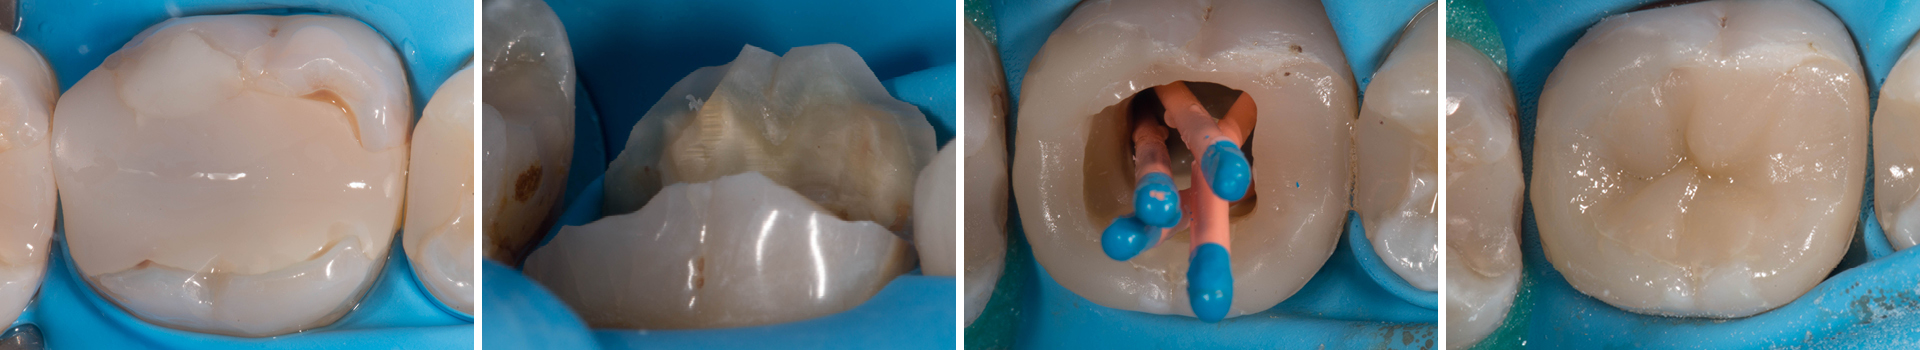

Abbildung 3

Initiale Zugangskavität: Mit einem Rosenbohrer wurde die alte Guttapercha reduziert. Für den Prä-Endo Aufbau wurden sowohl mesial als auch distal die Höcker partiell eingekürzt. Dies senkt das Frakturisiko bis zur indirekten Post-Endo Restauration.

Abbildung 4

Darstellung der partiellen Höckerreduktion von bukkal. Einkürzung um ungefähr 1,2 mm.

Abbildung 5

Für eine optimale Form des Approximalbereich wurden Matrizen und Holzkeile angelegt. Die Größe S sorgt für eine gute Position vom Kontaktpunkt. Da die Nachbarzähne noch restauriert werden, wurde hier auf einen Spannring verzichtet.

Abbildung 6

Initiale Entfernung der alten WF mit 2500 rpm. Dabei entsteht oft dieses Bild, bei dem die alte Guttapercha am Instrument hängen bleibt. Während der Revision wurde mit NaOCl gespült, welches zuvor mit einem milden Chelator gemischt wurde. Danach erfolgte eine elektrische Längenmessung mit einer Handfeile. Der Zahn wurde temporär mit Komposit verschlossen - eine medikamentöse Einlage erfolgte mit 2%-Chlorhexidin-Gel.